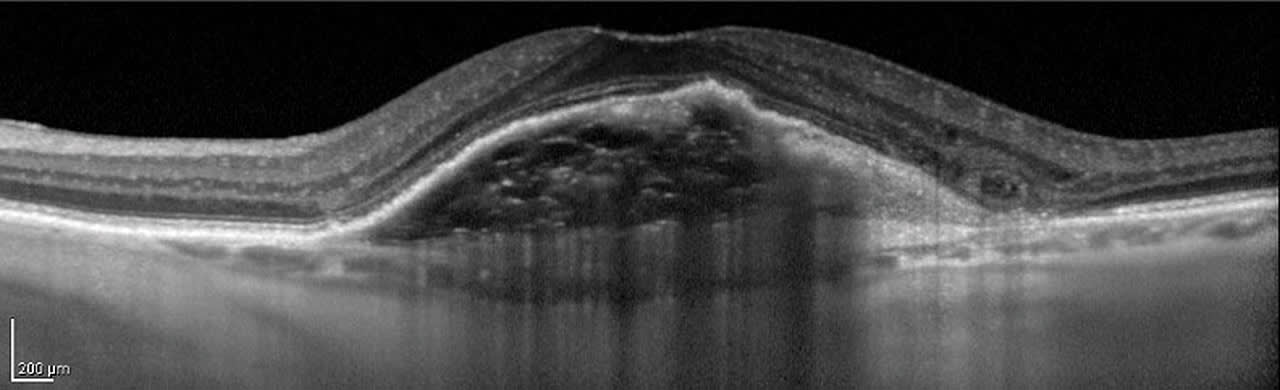

EDI is a very useful tool in evaluating nevus vs tumor in the choroid, as the posterior edge of a mass is reflective, allowing for more accurate measurements (Figure 3).